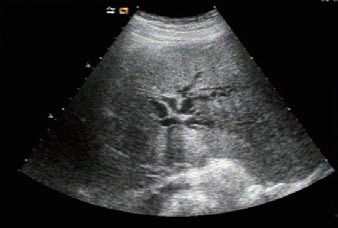

(4)强回声团远端小胆管轻至中度扩张,出现平行管征(图5-17)。

图5-16 肝内胆管结石(多发性、条索状、柱状、树枝状、铸型)

图5-17 肝内胆管扩张(箭头所指:平行管征)